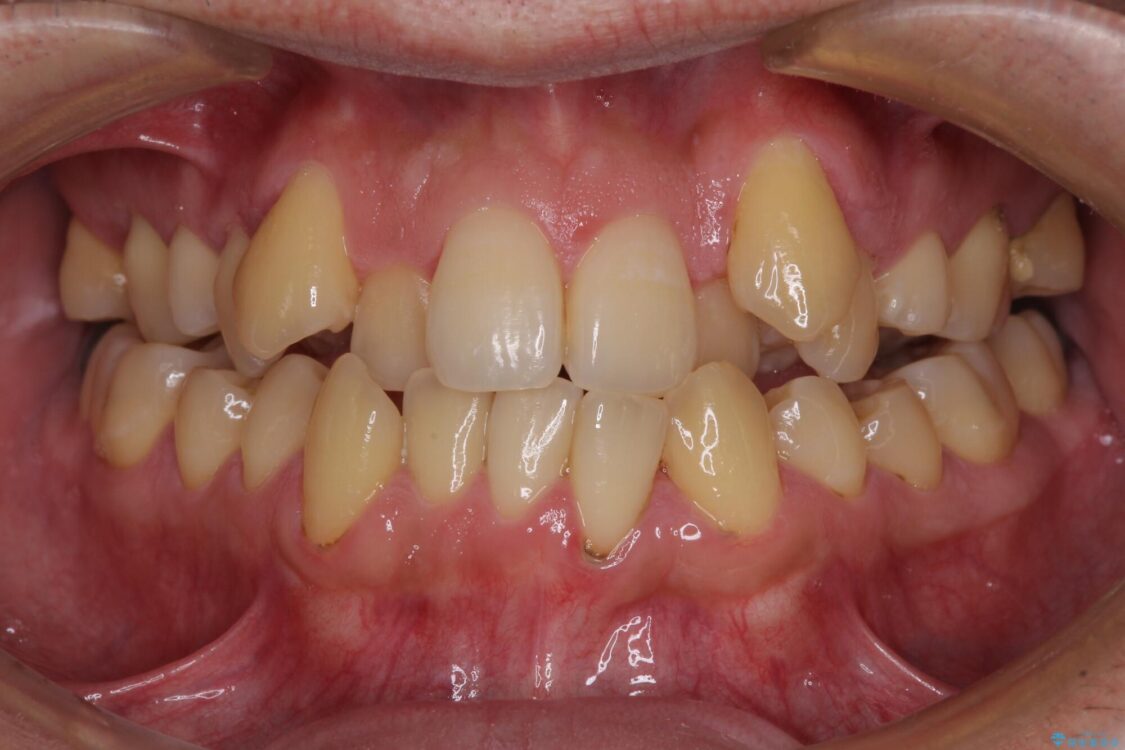

八重歯と前歯のクロスバイトを改善したいとのことで来院された患者様です。

デコボコの程度は強かったのですが、口元の突出感はなかったため、非抜歯矯正としました。

治療前

• 八重歯とクロスバイト 目立たないワイヤー装置で矯正治療 治療前画像